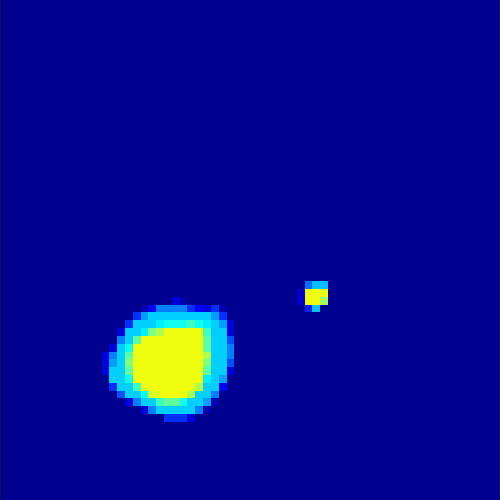

The parameters α𝛼\alpha, β𝛽\beta and δ𝛿\delta were optimized by comparing the final results with the existing ground truth in both cases. Here we mention that the choice of parameters is not a trivial task, since the result strongly varies with a change in the parameters. In figure 5, the scaling between the error in the L2superscript𝐿2L^{2}-norm between exact and reconstructed image sequence per pixel per time step and the choice of each parameter out of a certain range is displayed examplarily for the heart data set. Here, we chose α[0,0.5]𝛼00.5\alpha\in[0,0.5], β[0,1]𝛽01\beta\in[0,1] and δ[0,2]𝛿02\delta\in[0,2] and kept two parameters fixed while plotting the error in the third one. The adaption of parameters in case of real data and, if possible, the elimination of some of them remains a future task.

Refer to caption

(a) Error scaling for α𝛼\alpha

(b) Error scaling for β𝛽\beta

(c) Error scaling for δ𝛿\delta

Figure 5: L2superscript𝐿2L^{2}-error between exact and reconstructed data for different regularization parameters for the first data set (for given data without noise)